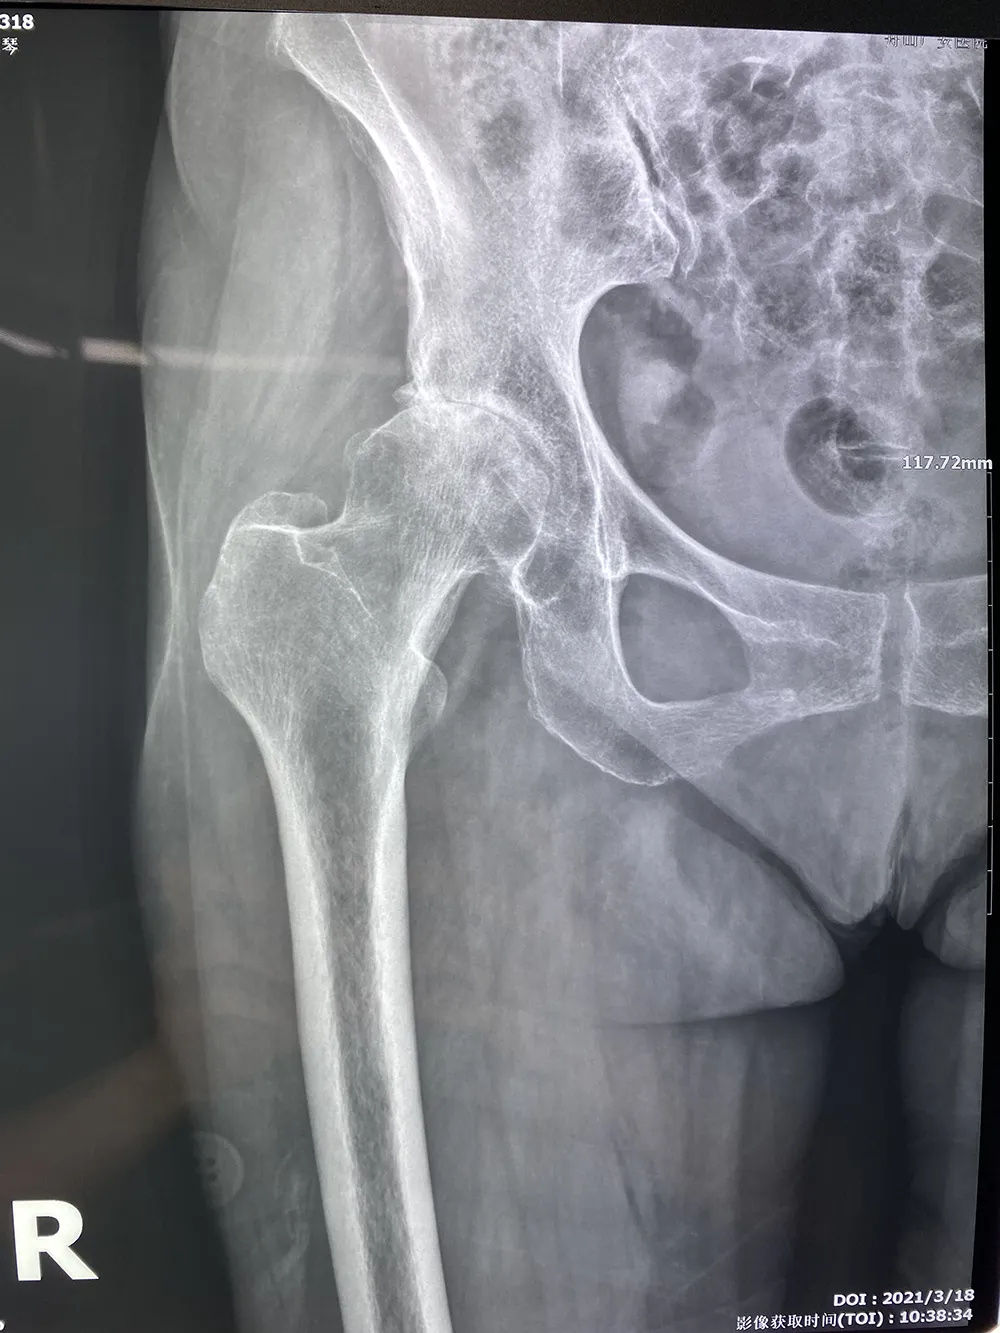

↑術(shù)前拍片提示右股骨頭壞死,髖關(guān)節(jié)骨性關(guān)節(jié)炎

近日,75歲的倪阿姨因右髖關(guān)節(jié)疼痛不適10余年,加重伴活動受限半年,無法行動,診斷為“右股骨頭壞死,右髖關(guān)節(jié)骨性關(guān)節(jié)炎”。廣安醫(yī)院骨科中心羅軍主任團隊運用先進的人工智能髖關(guān)節(jié)置換術(shù)前三維輔助規(guī)劃系統(tǒng)幫助患者精準術(shù)前規(guī)劃,術(shù)后第一天患者即可下地行走。

現(xiàn)年76歲的倪阿姨,平時有慢性支氣管炎、腦梗死、骨質(zhì)疏松癥、腰椎間盤突出等多種基礎(chǔ)病。曾在多家醫(yī)院就診,均建議其行人工髖關(guān)節(jié)置換術(shù),患者因擔心手術(shù)的并發(fā)癥拒絕手術(shù)治療,近半年右髖關(guān)節(jié)疼痛難忍,無法行走來我院就診。